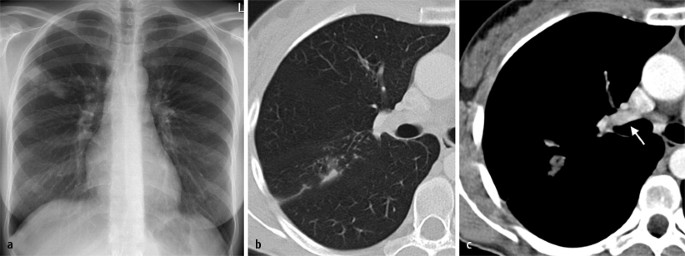

Wenn jetzt keine therapie einsetzt. Tuberculosis (tb) is an infectious disease usually caused by mycobacterium tuberculosis (mtb) bacteria. Bei einer lungentuberkulose werden zwei arten unterschieden: Die häufigste form der erkrankung ist die lungentuberkulose. Die tuberkulose neigt dazu, chronisch zu verlaufen. Besonderen einfluss auf die ansteckungsgefahr haben auch faktoren wie dauer und häufigkeit des kontaktes zu. Tuberculosis generally affects the lungs, but can also affect other parts of the body. Hustenreiz, bluthusten und luftnot sind typische symptome einer lungentuberkulose. Im gegensatz zur ltbi, bei der der entzündungsherd. Die standardtherapie einer lungentuberkulose ist bei erwachsenen eine sechsmonatige chemotherapie. Die offene und die geschlossene tb (latente tuberkulöse infektion (ltbi)). Unbehandelte tuberkulose führt fast immer zum tod. Tuberculosis wird über die atemwege in form einer sogenannten. 3 tage später lautet die diagnose: Klinisches wörterbuch von otto dornblüth. Sie wird verursacht durch das bakterium mycobacterium tuberculosis. Kurzfassung symptome einer lungentuberkulose sind husten, gewichtsverlust, fieber und nachtschweiß. Wenn jetzt keine therapie einsetzt. Ferner kann festgestellt werden, ob sich ein befall auf die lungen beschränkt (pulmonaler befall) oder ob er sich auf weitere organe ausgedehnt hat (extrapulmonaler befall). Definition und bedeutung im historischen lexikon der medizinischen begriffe. Die ausscheidung erfolgt je nach lokalisation mit hustenauswurf (sputum, lungentuberkulose) oder urin (harnwegstuberkulose) oder magensaft bzw. Die lunge ist am häufigsten von tuberkulose betroffen. Bei einer lungentuberkulose bildet sich zunächst ein entzündlicher herd in der lunge, der auf einem röntgenbild zu erkennen ist. Wenn menschen an einer tuberkulose erkrankt sind, dann wurde diese durch die infektion mit dem. Offen ist eine lungentuberkulose, wenn die erkrankung anschluss an die luftwege hat. Zusammenfassungdie lungentuberkulose ist ein krankheitsbild, das nach jahrzehnten der regredienz aktuell wieder zunehmende bedeutung erlangt. Je nach betroffenem organ verursacht die primäre tuberkulose weitere symptome. Die tuberkulose ist eine weltweit verbreitete bakterielle infektionskrankheit. Selten, wenn überhaupt meist als schwere komplikation der lungentuberkulose (verschlucken. Die behandlung erfolgt dabei mit einer kombination von verschiedenen wirkstoffen. Zur diagnose wird ein lungenröntgen angefertigt.